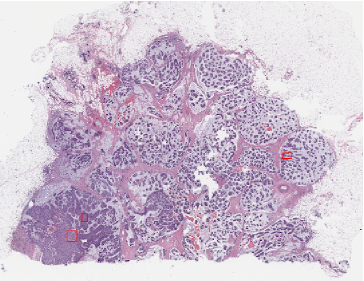

In Figure 3 (4), we report some examples of the 646464 attention filters for each of the two sets of attention maps that were generated by FT-R34-AC (PT-R34-AC) for two different WSIs with tumors, for dataset Camelyon 16 (TUPAC16). The filters of the set of the max pooling-based attention maps (AMp𝐴𝑀𝑝AMp) highlight specific features on critical regions, while the filters of the set of the min pooling-based attention maps (Amp𝐴𝑚𝑝Amp) compute a complementary attention inducing a more effective feature learning. Indeed, it can be noted from Figures 3 and  4 that Amp𝐴𝑚𝑝Amp provides a lower but more diffused response, so leading the model to consider a higher number of patches but with a lower confidence degree.

Refer to caption

Figure 3: Examples of some attention maps for Camelyon 16, generated by different sets of attention modules which highlight specific features of the tumor class. The first column shows WSIs from the test set for which the tumor location is underlined in blue. The second to fourth columns show the selected attention modules for the input images from different set of attention maps (i.e., the first and third rows for the max-pooling-based attention maps; the second and fourth rows for the max-pooling-based attention maps). The highest attention weight is denoted in white color and the lowest in black.